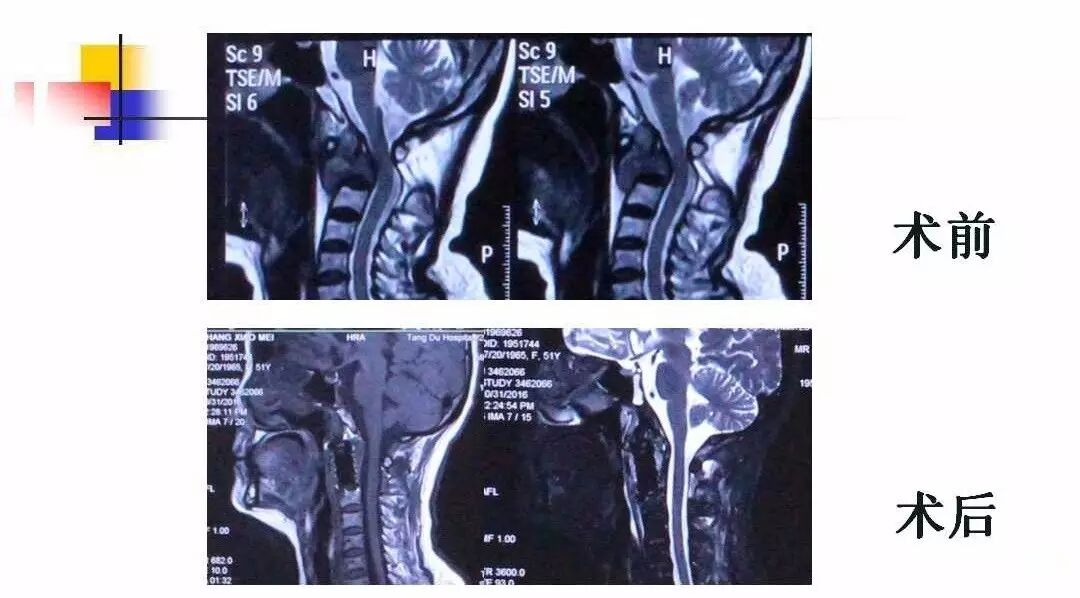

在脊柱神经外科、显微神经外科和颅底肿瘤外科前沿研究和临床诊治领域有着扎实的基础,为全国首批获得脊柱神经外科医师培训认证的神经外科医生。擅长颈椎病、椎管肿瘤及各种脊柱疑难疾病的诊治、脑肿瘤微创手术,尤其擅长颈椎退行性疾病的手术,率先在国内开展了颅底凹陷后路复位、颈前路减压融合等高难度手术,多年来收治了来自全国各地的大量患者,疗效达到国内领先水平。